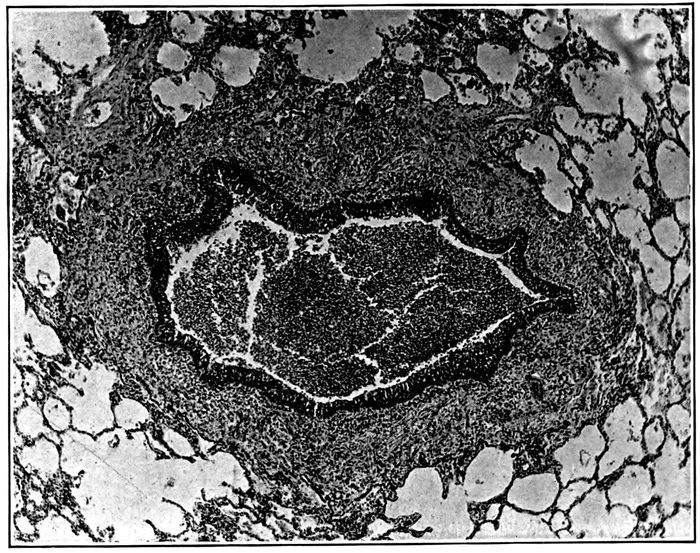

17. Acute bronchiectasis showing fissures penetrating into bronchial wall and at one place entering alveolar tissue 246

18. Acute bronchiectasis showing fissures in the bronchial wall extending into neighboring alveoli which in zone about are filled with fibrin 247

19. Acute bronchiectasis; the bronchial wall indicated by engorged mucosa shows a varying degree of destruction, fissures extending into and through the bronchial wall 248

20. Acute bronchiectasis with destruction of bronchial wall exposing alveoli filled with fibrin 249